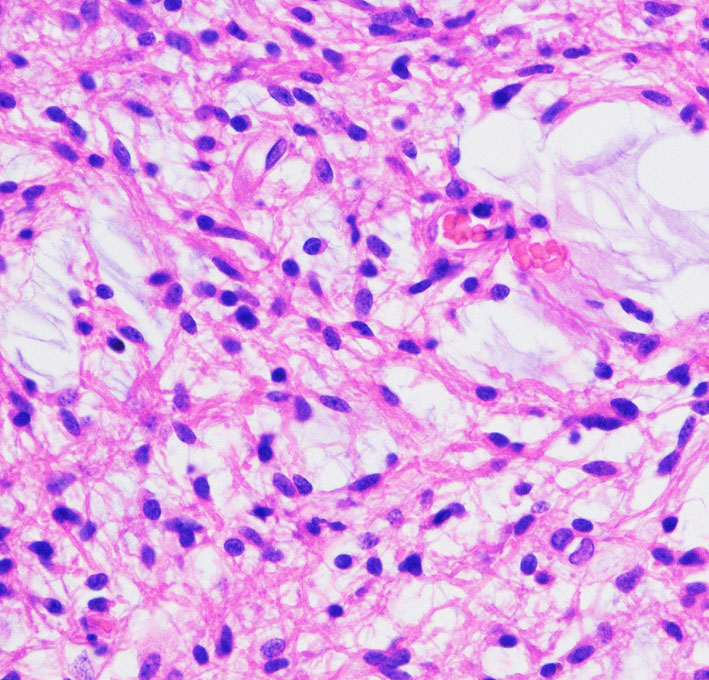

病理所見では,幼児型のpilomyxoid astrocytomaの部分が混在します。その部分が増殖と腫瘍増大に関わっています。T2強調画像で高信号でガドリニウム増強される部分です。

myxoidな部分です。右下のMIB-1染色では3%ほどの陽性率であり,数年単位では腫瘍増大があり得ることを示します。柔らかく出血性で吸引摘出できる部分の腫瘍です。IDH wild type, BRAFV600 wild type, H3K27 wild type, FGFR1 N546K mutationでした。

厚く肥厚した視神経鞘の内部の視神経組織はほとんど腫瘍に置き換わっていて,GFAPで染色され高度の石灰化を伴います。これは腫瘍というよりも瘢痕化してしまった,adult-type pilocytic astrocytomaに認められる所見です。

Rosenthal fiber, eosinophyric granular body, psammoma bodyなどが認められ,成熟しきって退行変性に移行するpilocytic astrocytomaの像です。この部分は増大しません。線維性に極めて硬い組織です。